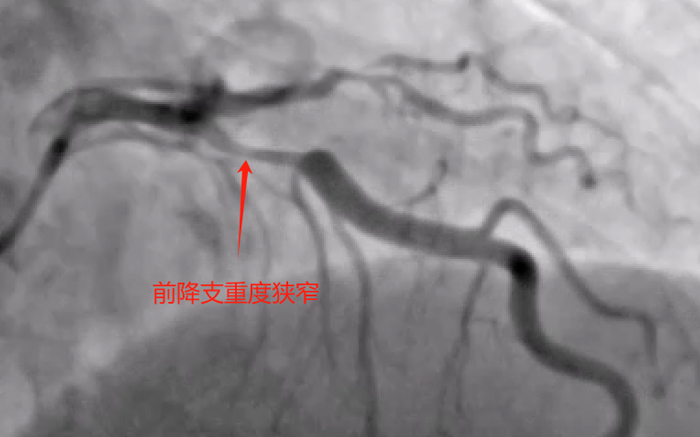

造影可见:左冠双开口,前降支近端及回旋支近端均重度狭窄;右冠极度扭曲,中段中度狭窄,远端中度狭窄伴溃疡形成,后三叉处及后降支极重度狭窄。造影结果比我预想的结果要差,多支血管病变,而且右冠病变很复杂。